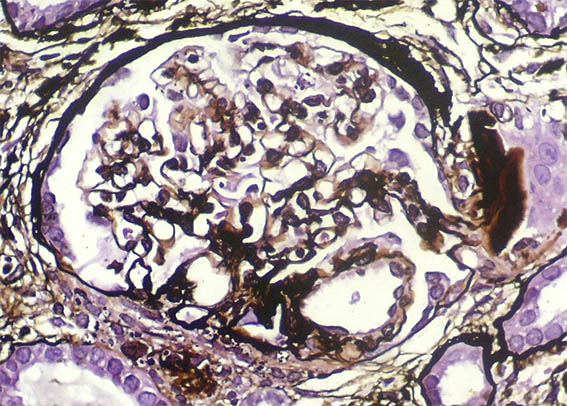

Figura 10. Plata-metenamina, X400.